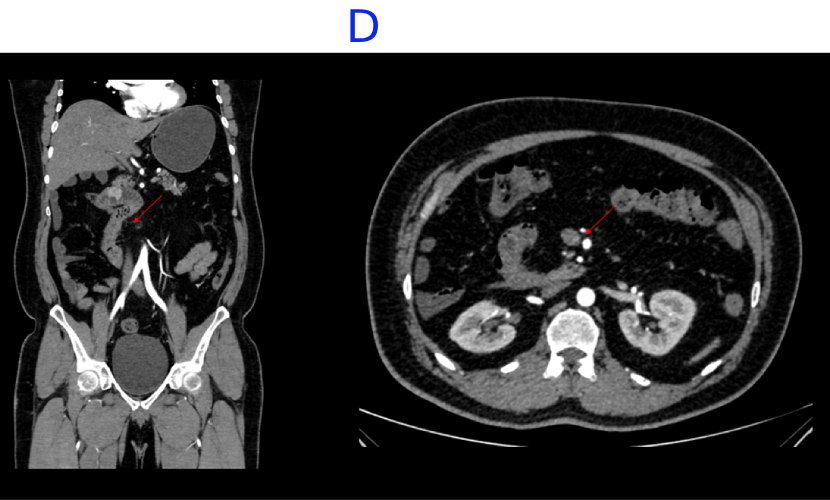

D. Incidental note of malrotation with the duodenojejunal junction lying to the right of the midline and altered SMA-SMV relationship.